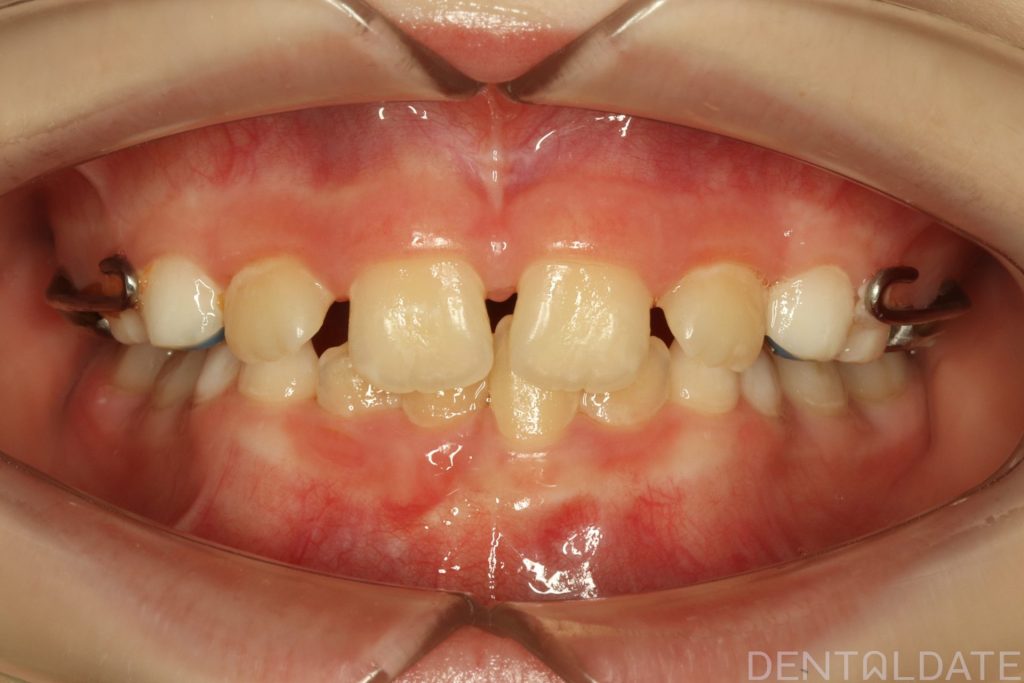

The patient had been undergoing orthodontic treatment at another clinic for 1.5 years with no significant progress.

With a new treatment plan in place -the anterior bite was normalized within just one week.

We are now focused on final adjustments to tooth alignment and occlusal height.